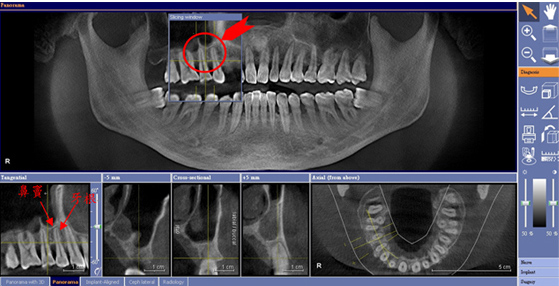

確認正確的牙根數量及方向